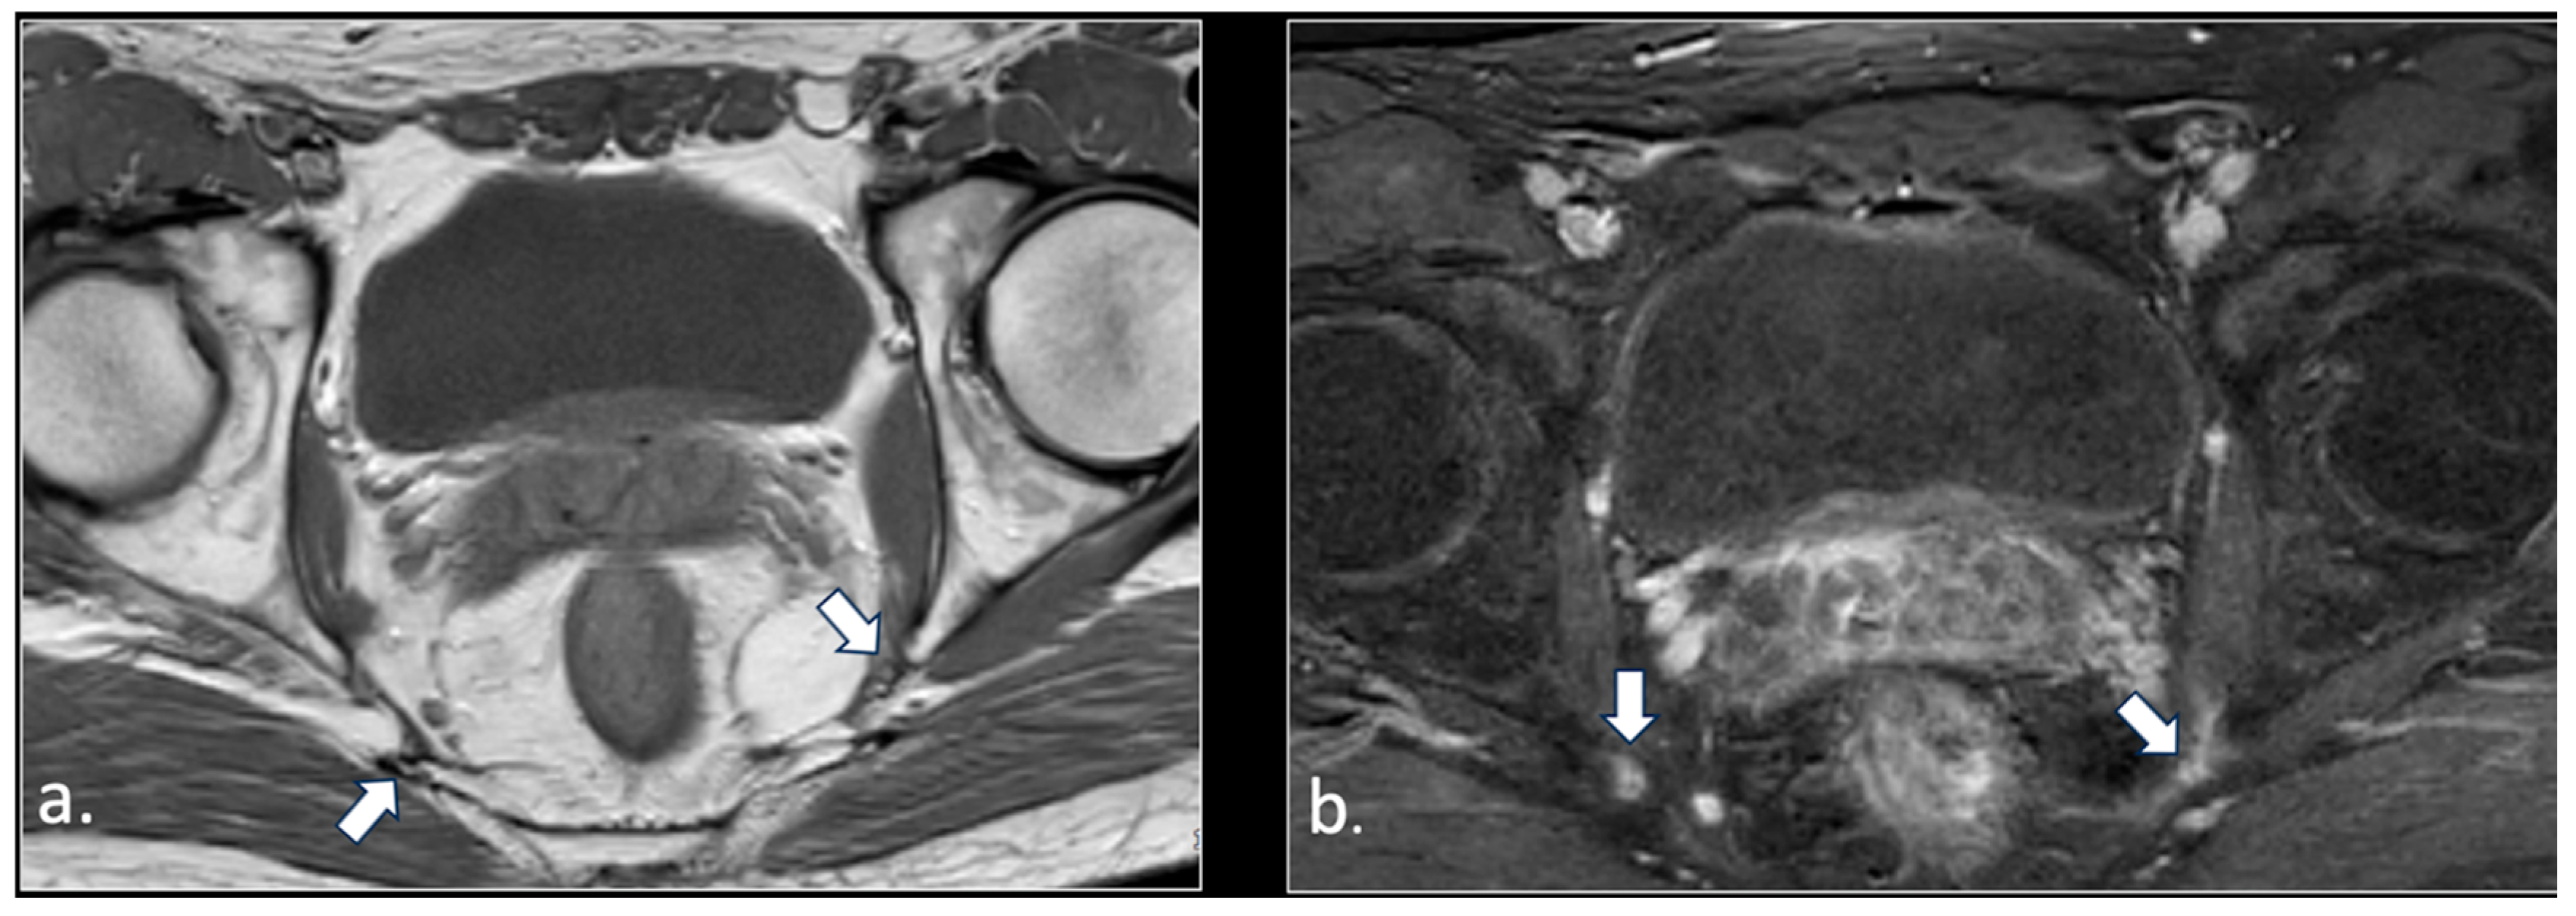

- Perineal fibrosis involving Alcok’s canal (4 patients);

- Giant cyst of the prostatic utricle (1 patient);

- Pudendal nerve schwannomas (2 patients);

- Varices of the pudendal vein in the Alcock canals (2 patients).